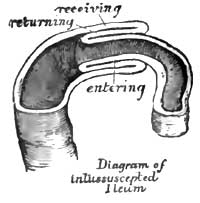

| 26. | SIMPLE INVAGINATION OF THE ILEUM |

| 27. | SIMPLE INVAGINATION, WITH OCCLUSION OF BOWEL, FROM INFLAMMATORY CHANGES |

| RHEUMATISM. | PURPURA. |